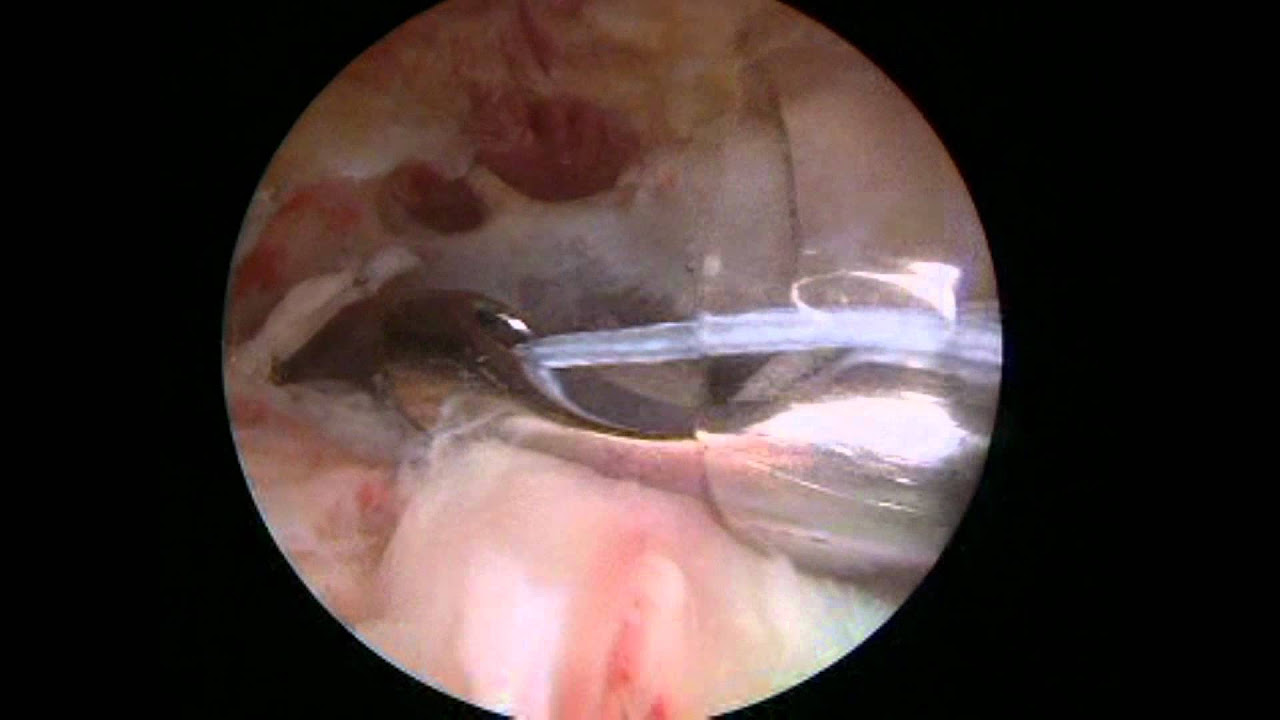

Arthroscopic Rotator Cuff Repair with a Double-Row Technique